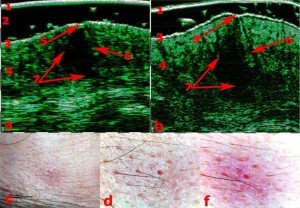

Η διαφοροποίηση μεταξύ των Υπερτροφικών Ουλών (1η εικόνα) και των Χηλοειδών (2η εικόνα) με τη βοήθεια του Υπέρηχου Υψηλής Συχνότητας.

Φλύκταινες (1η εικόνα) και συνδυασμός οζιδίων και κυστών (2η εικόνα). Οι πιο έντονες αλλαγές εντοπίζονται στο πάχος του χορίου. Σαρώσεις με Υπέρηχο Υψηλής Συχνότητας και Βιντεοδερματοσκοπικές απεικονίσεις.

ΔΙΑΦΟΡΟΠΟΙΗΣΗ ΜΕΤΑΞΥ ΥΠΕΡΤΡΟΦΙΚΩΝ ΟΥΛΩΝ ΚΑΙ ΧΗΛΟΕΙΔΩΝ

Οι ουλές του δέρματος αποτελούν ένα από τα πολύτιμα θέματα στην δερματολογία και την αισθητική ιατρική. Σύμφωνα με ορισμένες πρόσφατες μελέτες, ελήφθησαν δεδομένα HFUS για τη διαφοροποίηση των διαφόρων τύπων ουλών.

Οι μετρήσεις ουλών HFUS και η ανάλυση των μοτίβων χρησιμοποιήθηκαν με επιτυχία για τη διαφοροποίηση των νορμοτροφικών, υπερτροφικών, χηλοειδών και ατροφικών ουλών. Αυτές οι κλινικές πληροφορίες είναι ζωτικής σημασίας για την ορθή θεραπεία και αποκατάσταση των ουλών.

Η διαφοροποίηση μεταξύ των υπερτροφικών (αριστερά) και των χηλοειδών ουλών (δεξιά).